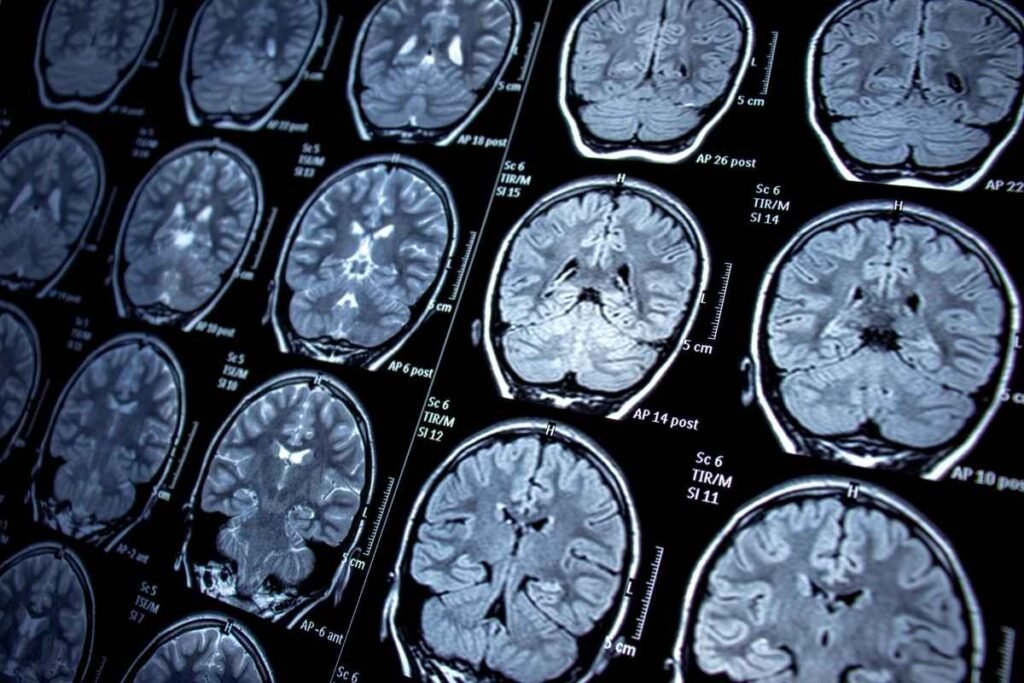

La medicina avanza hacia una nueva frontera en el tratamiento de la epilepsia. En lugar de limitarse a controlar los síntomas con fármacos, los científicos están buscando cómo “reparar” los circuitos del cerebro que originan las crisis epilépticas. Así lo explica el Dr. Jonathon J. Parker, neurocirujano de Mayo Clinic en Phoenix y director del Device-Based Neuroelectronics Research Lab, quien lidera un conjunto de investigaciones que podrían cambiar la forma en que se trata esta enfermedad que afecta a más de 50 millones de personas en el mundo, según la Organización Mundial de la Salud (OMS).

La epilepsia es una de las enfermedades neurológicas más comunes del planeta. Puede aparecer a cualquier edad y tener distintas causas: factores genéticos, lesiones cerebrales, tumores, accidentes cerebrovasculares o infecciones. En muchos casos, la causa exacta sigue siendo un misterio.

Neuromodulación: consiste en el uso de dispositivos que estimulan áreas específicas del cerebro mediante impulsos eléctricos. A diferencia de las cirugías tradicionales —que eliminan o destruyen la zona afectada—, la neuromodulación intenta “reprogramar” el funcionamiento neuronal.